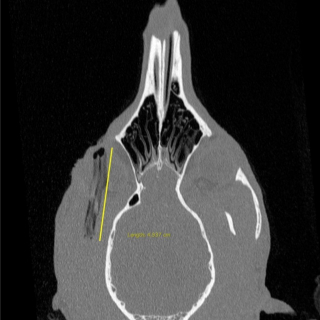

Juste avant les soins, les vétérinaires avaient réalisé un scanner au niveau de l’œil du chien pour mieux se rendre compte de la blessure. Après le scanner, ils se sont aperçus que le bâton était encore en un seul morceau et qu’il était logé juste au-dessus de l’œil de Mia. C’est une véritable chance pour la petite chienne : le bâton est ainsi plus facile à retirer pour les vétérinaires. Ces derniers parviennent à le faire sortir sans encombre.